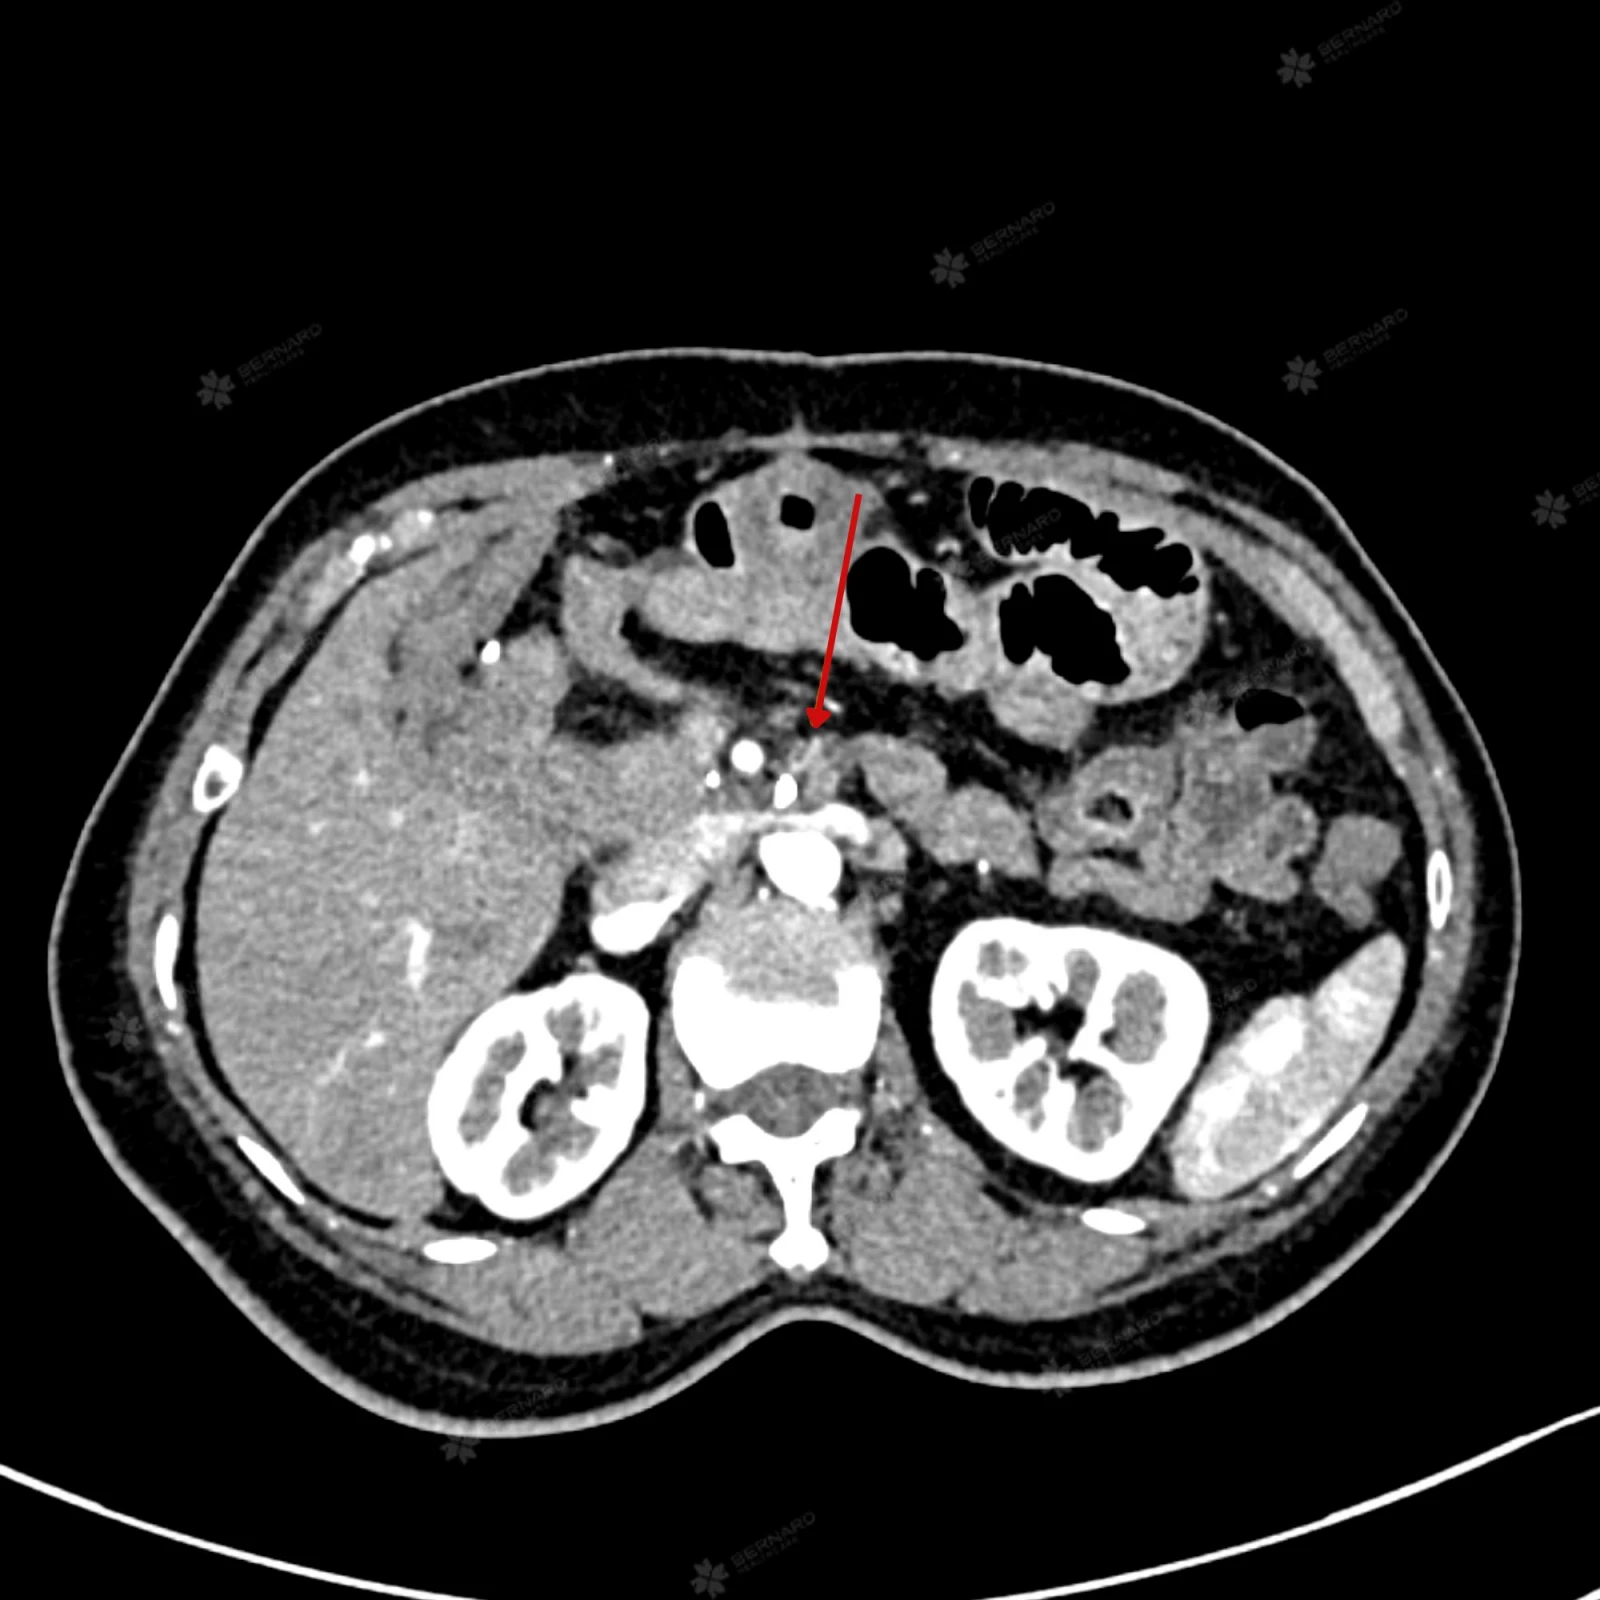

Kết quả ghi nhận:

Không phát hiện khối u tại phần tụy còn lại sau phẫu thuật cắt khối tá tụy. Tuy nhiên, phần mô mềm quanh thân tạng và động mạch gan chung, nghi ngờ là biến đổi hậu phẫu, cần theo dõi sát để loại trừ khả năng tiến triển bất thường.

Ngoài ra, ảnh chụp CT vùng bụng của bệnh nhân còn cho thấy hạch to rải rác vùng cạnh động mạch chủ bụng, chưa có bằng chứng rõ về xâm lấn mạch máu nên không thể loại trừ hoàn toàn nguy cơ di căn. Bệnh nhân cần được lên kế hoạch chăm sóc chặt chẽ, tiếp tục theo dõi sát qua hình ảnh và thăm khám chuyên khoa định kỳ.